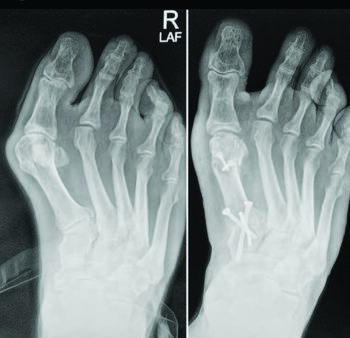

The surgeon places fixed-angle locking plates and screws across the normal anatomic contours of the second and third TMTs, and the plates rest on the midline of the bones. This natural angled position, oriented from lateral to medial, assures the screws enter the center of each bone. Maintaining ligamentous attachments further stabilizes the hardware. The surgeon can then reduce the first ray, with the TMT prepared similarly to maintain correction through realignment arthrodesis.30 Complete correction of the true intermetatarsal angle is made possible through initial correction of the lesser ray position and midfoot deformity. This results in reduction of foot width and predictable improvement in the radiographic angular relationships of the medial column.31,32